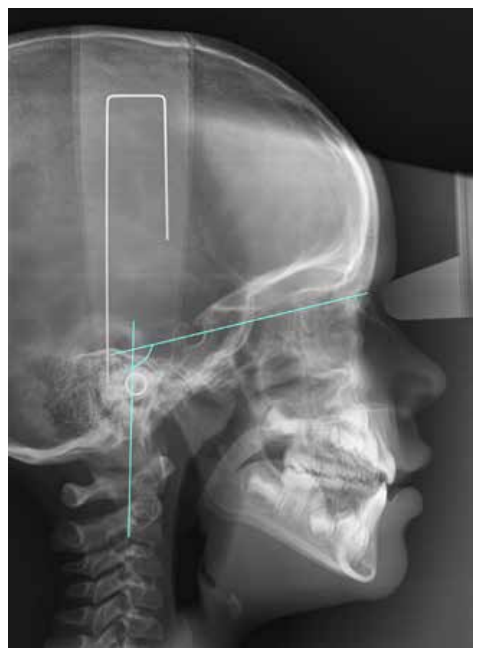

Craniocervical posture was assessed via the variables OPT-SN, which refer to the angle formed by SN and the line that runs through the most postero-superior and postero-inferior point of the odontoid process (Figure 1).